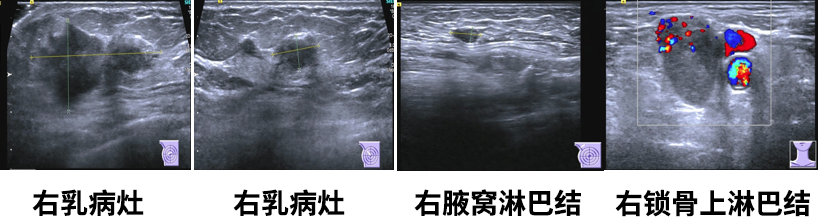

乳腺彩超

1.右乳肿物(约5.0*2.4*4.7cm),乳腺癌可能,BI-RADS5;

2.左乳切除术后,左胸壁未见明显异常;

3.右腋下(1.0*0.5cm)及右侧锁骨上淋巴结(2.6*1.8cm),转移可能。